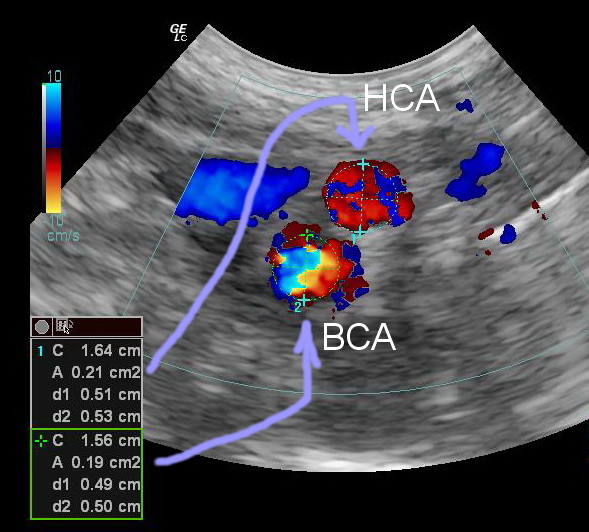

Средний внутренний диаметр наружной сонной артерии у женщин больше, чем у мужчин.

Р.S. Архитектоника зоны бифуркации общей сонной артерии имеет половые и возрастные особенности, которые оказывают значительное влияние на распределение потоков крови, напряжение различных участков сосудистой стенки данной зоны и, как следствие, локализацию атеросклеротического процесса.

Гистологическое строение сонных артерий находится в тесной связи с архитектоникой сосудистого русла. Расположение атеросклеротических бляшек и последовательность их образования определяются местными гемодинамическими характеристиками.

Из картинок видно, что соотношение ВСА/НСА у мужчин ближе к 1, у женщин >1

То есть относительно притока к головному мозгу, у женщин возможности выше, чем у мужчин. Отсюда выводы? (вопрос 3). Подумаем. Потом обсудим, как интерпретирует Оксфорд.